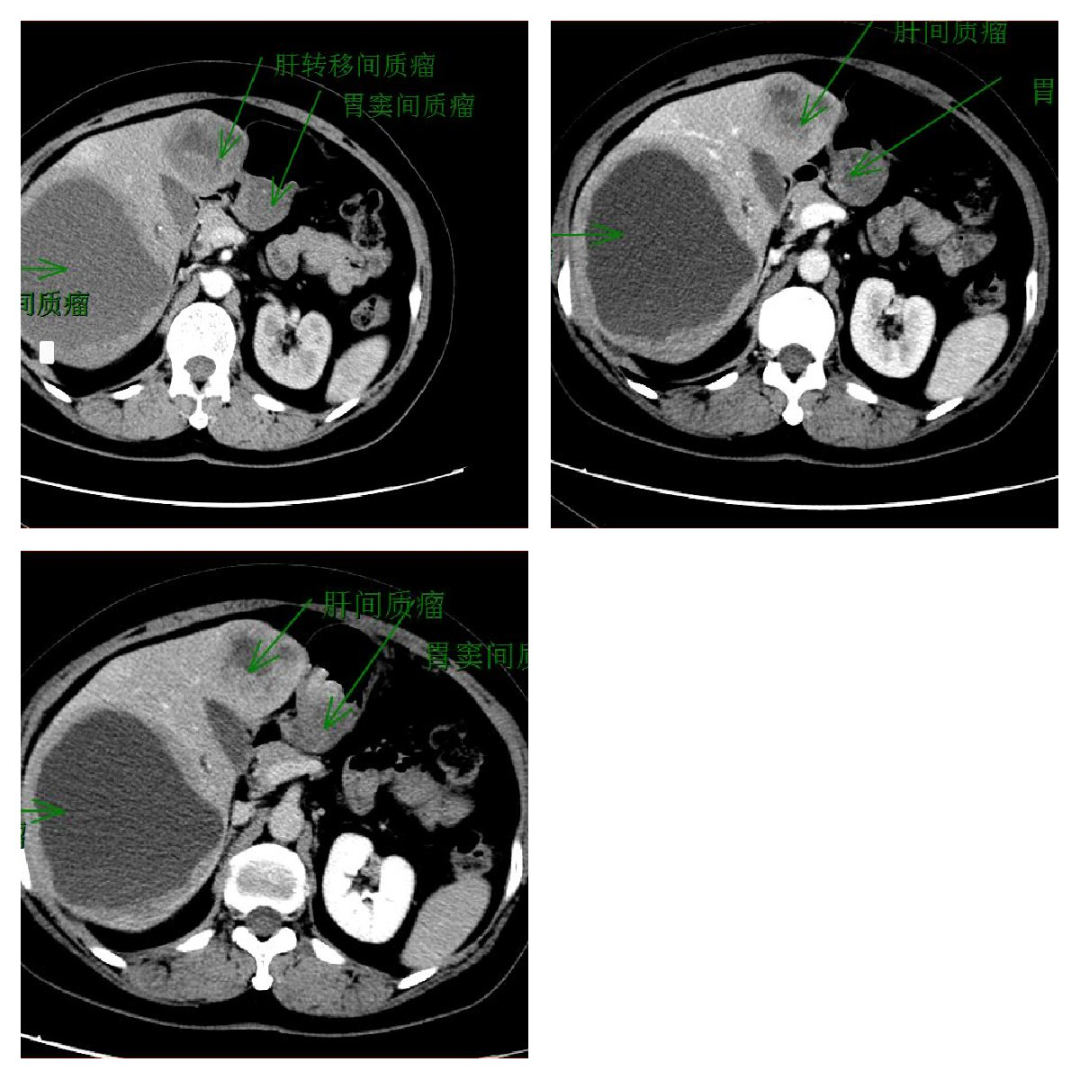

肝、胃间质瘤:胃肠比较容易出现间质瘤,肝往往为转移间质瘤;影像学特点是动脉期不均匀强化肿物影,与周围组织分界不清,向周围浸润。